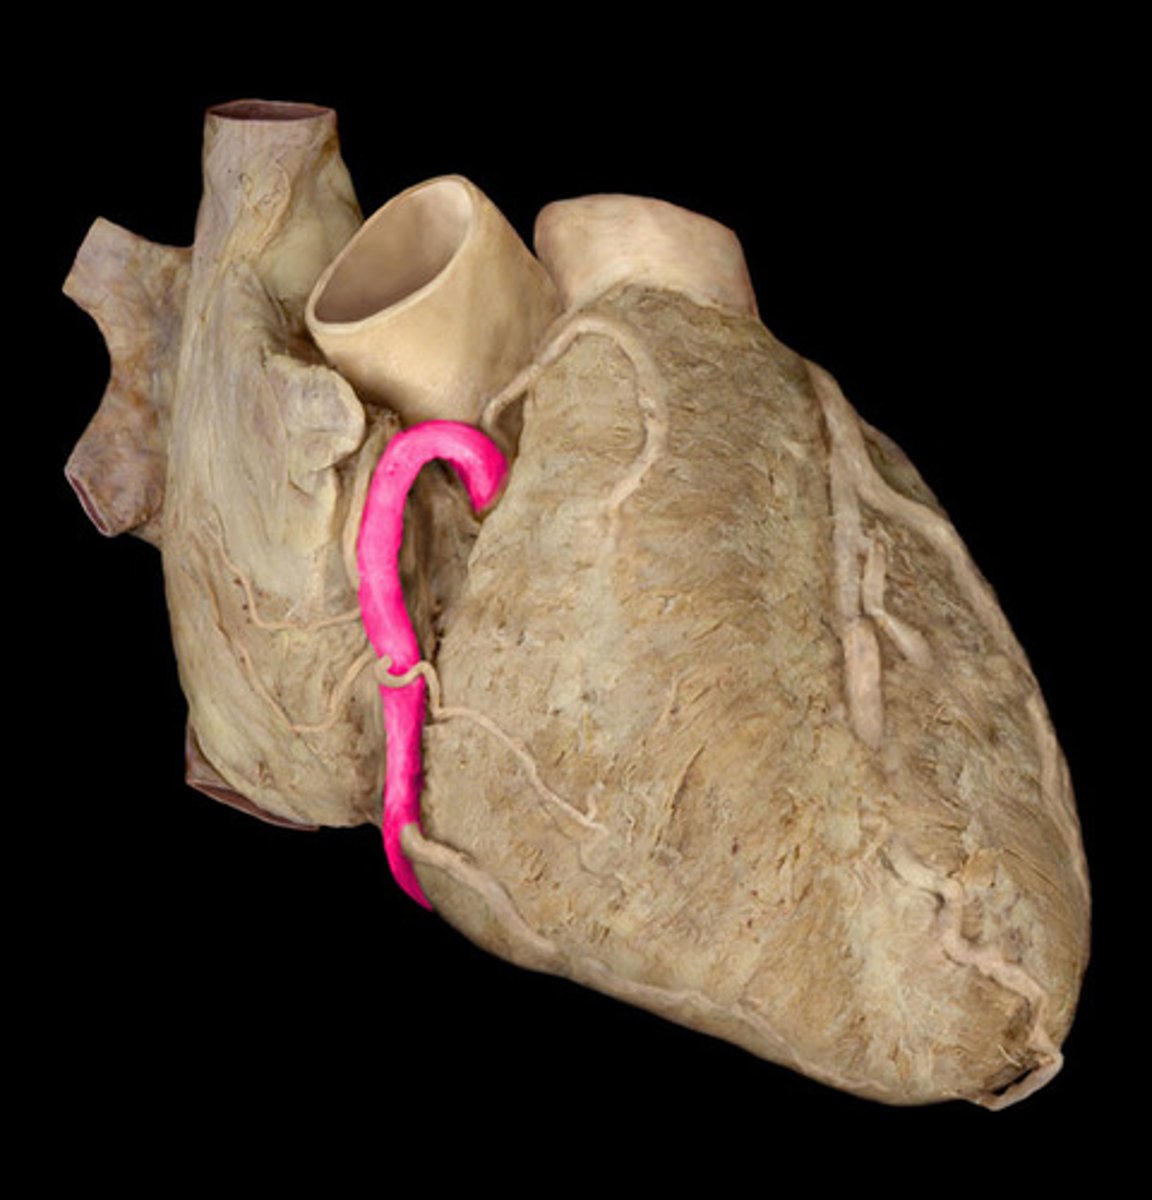

R coronary artery

st

pull right auricle back to show tube on anterior side

H1

16

R marginal artery

forms Y-shape off of coronary artery

1st branch off coronary artery